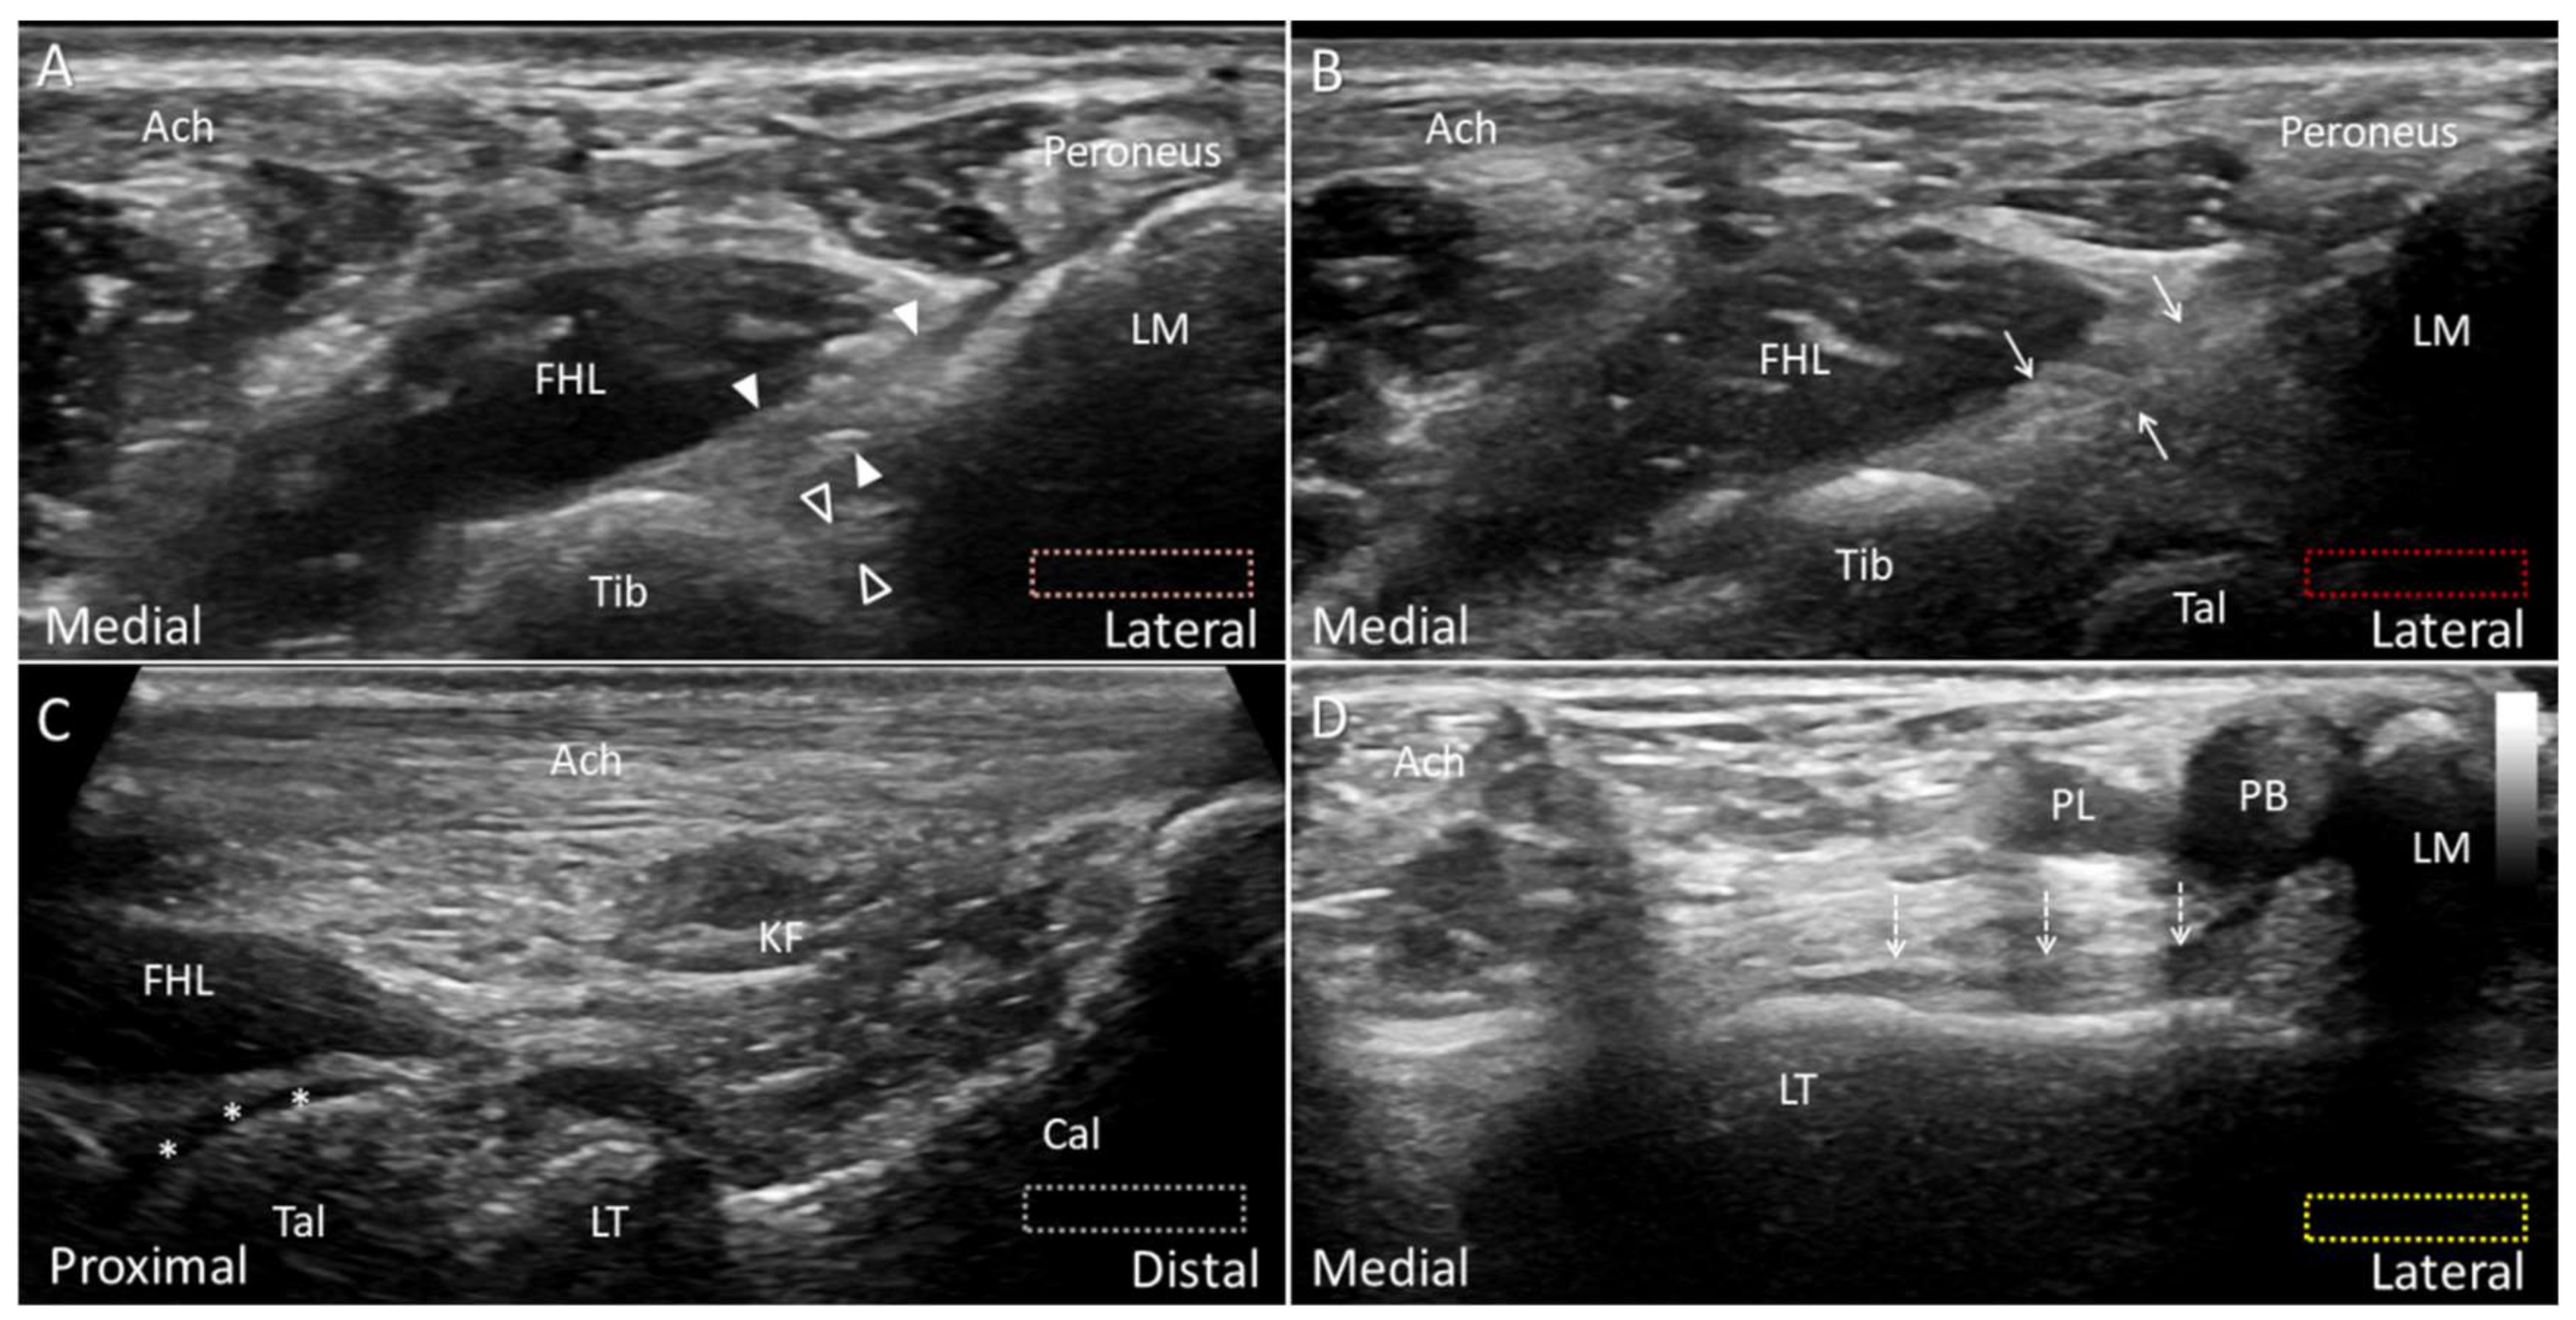

4.4. Plantaris Tendon

4.4.1. Anatomy

4.4.2. Scanning Technique

4.4.3. Clinical Relevance